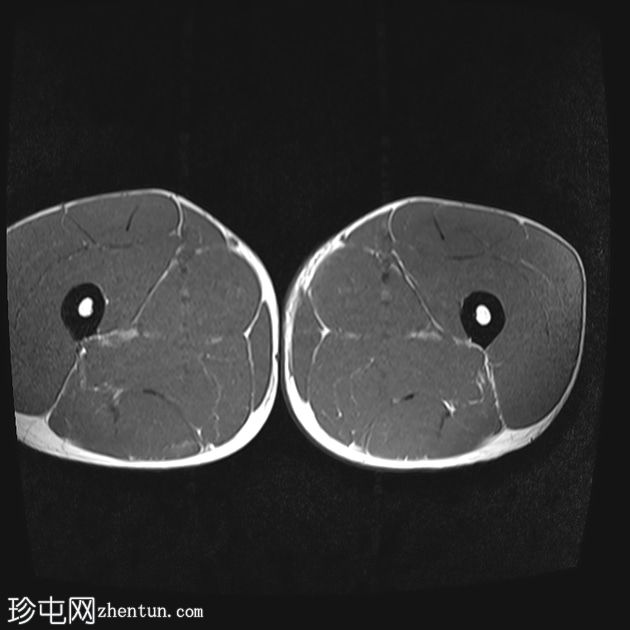

轴向

T1 tirm

收肌长肌腱从耻骨起点完全撕脱,可见充满液体的间隙(4毫米),肌腱近端回缩。

相关的肌内水肿累及收肌长肌、短肌和耻骨肌,筋膜间液沿股薄肌向内侧延伸。

MRI 表现与收肌长肌腱从起点撕脱并远端回缩相符,可见充满液体的间隙、筋膜间液和肌肉拉伤。

根据英国田径协会肌肉损伤分类(BAMIC),该损伤被归类为 4c 级。